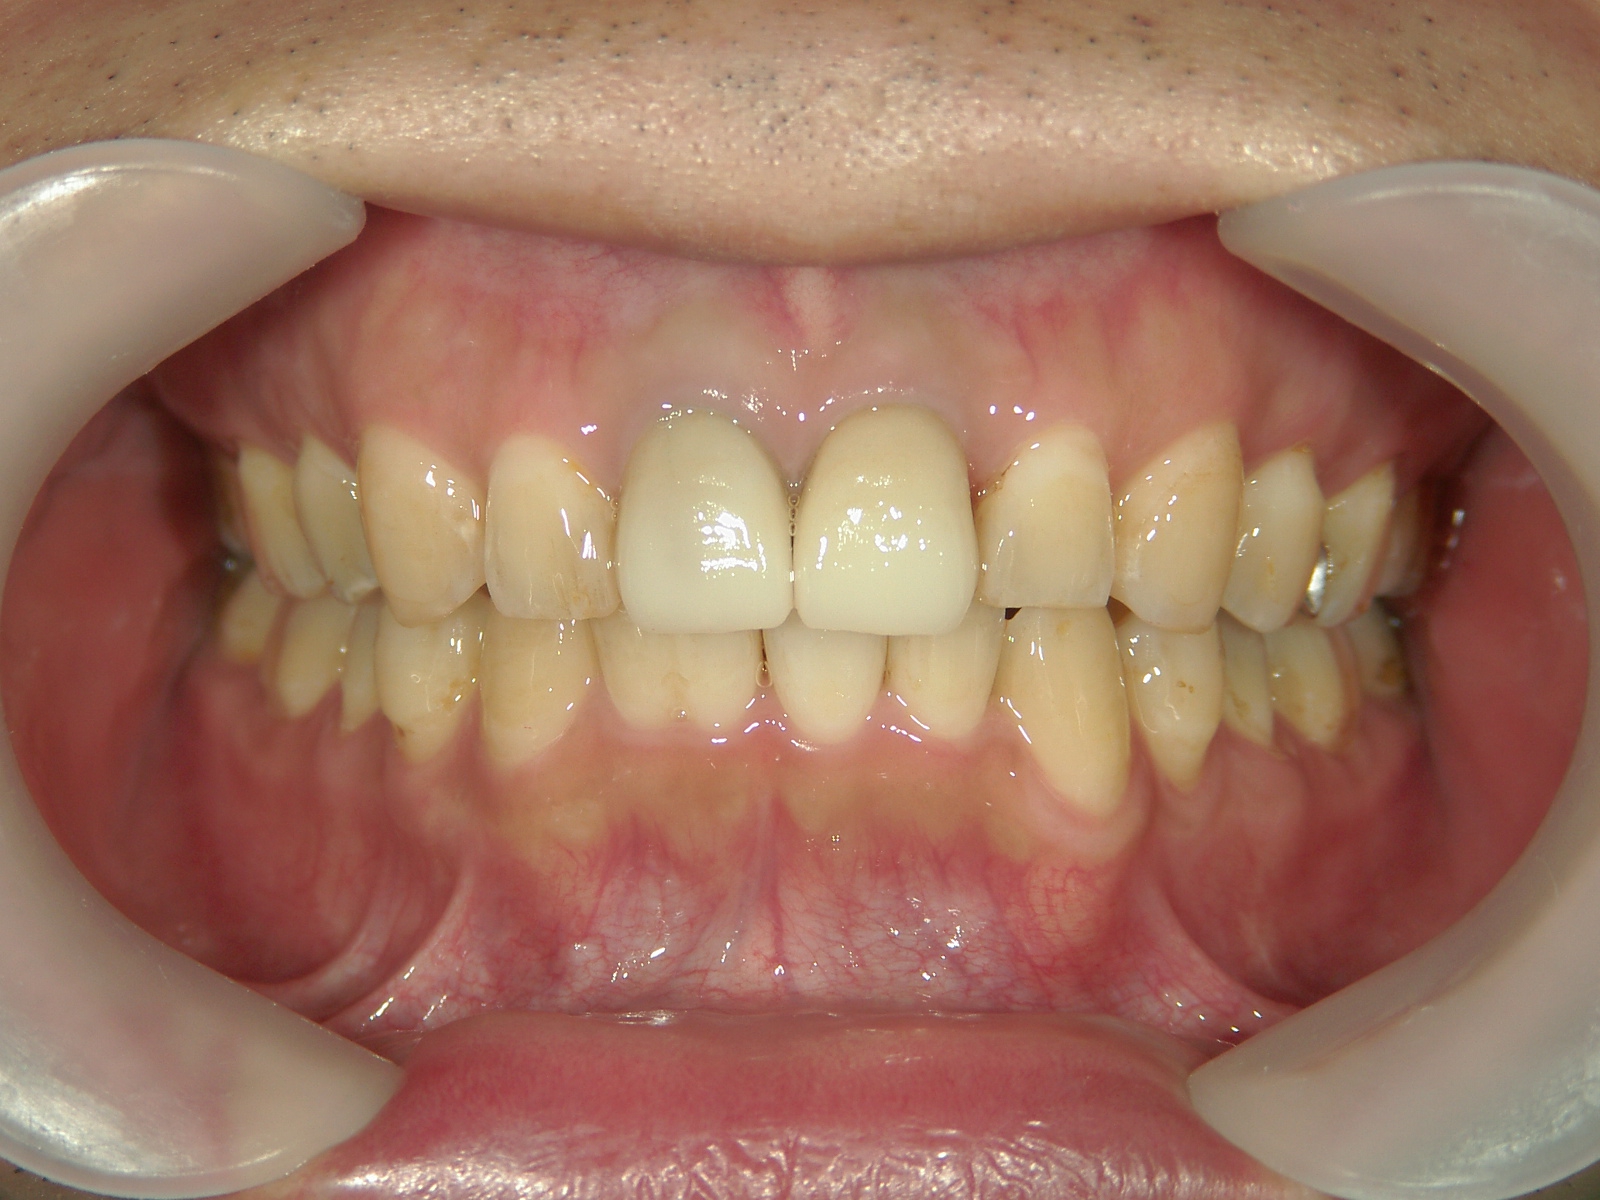

矯正歯科 治療後矯正歯科 全顎ワイヤー矯正 治療後矯正歯科(全顎ワイヤー矯正)治療後

矯正歯科 治療後 E-AMXというセラミックにて左右上1番を被せ直しました。